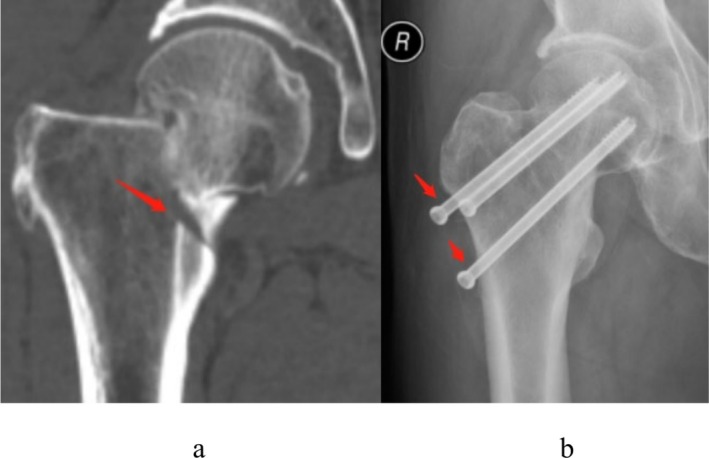

Methods: A retrospective analysis was conducted on 350 femoral neck fracture patients (aged 18-65 years) treated with closed reduction and three cannulated screws fixation at a single institution from 2015 to 2020. Evaluate the clinical and imaging information of patients such as sex, age, body mass index, Garden classification, calcar femorale injury situation, computed tomography Hounsfield units (CT HUs), comorbidities (e.g., diabetes, hypertension etc.) and complications (femoral neck shortening, nonunion, and femoral head necrosis). CT-based 3D reconstruction was used to analyze calcar femorale morphology. Statistical analyses included univariate and multivariate logistic regression to identify independent risk factors.